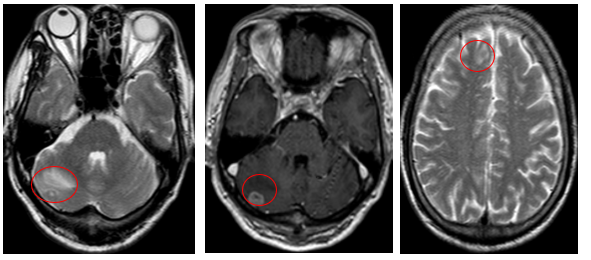

- Cộng hưởng từ sọ não (08/2025): Nhu mô bán cầu đại não, tiểu não phải, thái dương trái có các nốt lớn nhất đường kính 13mm, giảm tín hiệu trên T1W, tăng tín hiệu trên T2W, phù não xung quanh, ngấm thuốc mạnh sau tiêm – theo dõi tổn thương thứ phát

Hình 06: Bán cầu đại não, tiểu não phải, thái dương trái có các nốt lớn nhất đường kính 13mm, giảm tín hiệu trên T1W, tăng tín hiệu trên T2W, phù não xung quanh, ngấm thuốc mạnh sau tiêm

- Chụp cộng hưởng từ sọ não (11/2025): Nhu mô não hình dạng và cấu trúc bình thường, tín hiệu đồng nhất, ranh giới chất trắng và chất xám rõ. Không thấy tổn thương khu trú hoặc lan tỏa

Hình 13: Không còn thấy tổn thương di căn não vùng bán cầu tiểu não sau điều trị trên phim chụp

Hình 14: Không còn thấy tổn thương di căn não vùng thùy đỉnh sau điều trị trên phim chụp

- Trên phim chụp cộng hưởng từ sọ não: không còn ghi nhận các ổ tổn thương di căn di não, phù não.